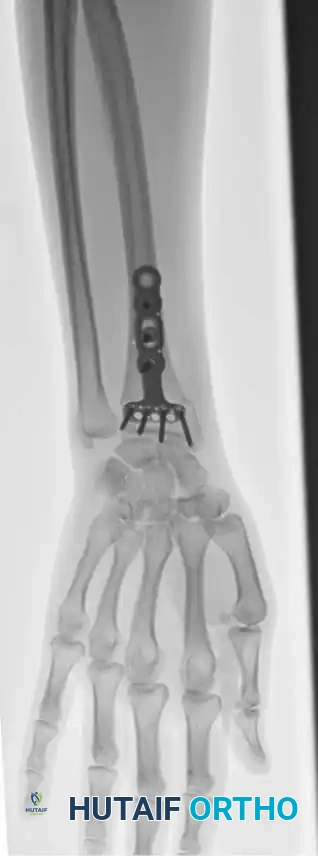

Open Reduction and Internal Fixation (ORIF)

Type II distal radial shear fractures (Barton type) usually require ORIF. These fractures are almost impossible to treat by closed means. Buttress plate fixation of volar Barton fractures is the gold standard.

Type III compression injuries require operative treatment if intraarticular damage is significant or radial shortening is severe. Careful restoration of the articular surface, radial angulation, and length is crucial. Fixation with multiple K-wires or plates is often necessary, and cancellous bone grafting is frequently required to fill impacted metaphyseal voids.

Often, a combination of open and closed techniques is necessary to treat Type III fractures satisfactorily.

Fig. 54-103 A and B, Four-part type III distal radial fracture treated by open reduction, internal fi xation of intraarticular component, iliac bone grafting, and external fi xation. C and D, Follow-up radiographs at 5 weeks (C) and 3 years (D) show anatomical restoration of joint surface, maintenance of radial length, and absence of degenerative changes. (From Fernandez DL: Fractures of the distal radius: operative treatment, Instr Course Lect 42:73, 1993.)

Fig. 54-103 A and B, Four-part type III distal radial fracture treated by open reduction, internal fixation of intraarticular component, iliac bone grafting, and external fixation. C and D, Follow-up radiographs at 5 weeks (C) and 3 years (D) show anatomical restoration of joint surface, maintenance of radial length, and absence of degenerative changes.